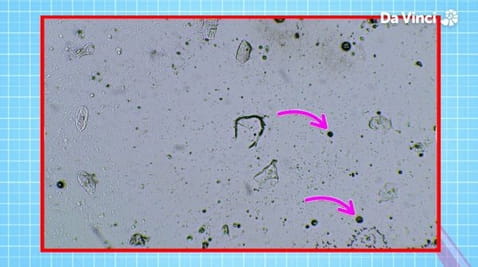

8. Widzenie od wewnątrz

7. Bakterie w organizmie i bioniczne oko